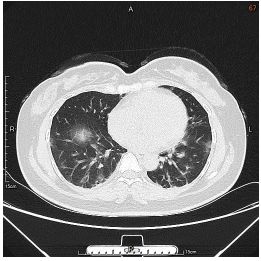

3. This 72-year-old diabetic man was taken to ER for productive cough for 10 days, and rapid progressive dyspnea for 2 days. He also had fever and chill for a week.